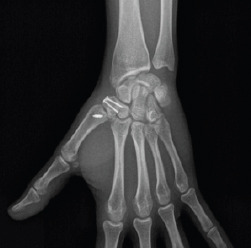

In the emergency department, dislocation closed reduction and temporary plaster cast immobilization were performed and surgical intervention was proposed. The patient underwent surgery 3 days after the trauma. A dorsal radial approach was used and identification and protection of the superficial radial nerve and radial artery branches were performed. Trapezium-metacarpal capsulotomy was performed. Anatomical trapezium fracture reduction was performed and fixed temporarily with Kirschner wire and definitively with two 1.5mm screws (Bone Care-Medartis). By the same approach, Bennett fracture fragments were excised and anterior oblique ligament was reinserted with 2.8mm mini-anchor (Twinfix). Finally, transarticular stabilization of the trapezium-metacarpal joint with Kirschner wire was performed to protect ligament repair. A cast immobilization was performed (Fig. 3).

Figure 3.

Post-operative X-ray: Anteroposterior view